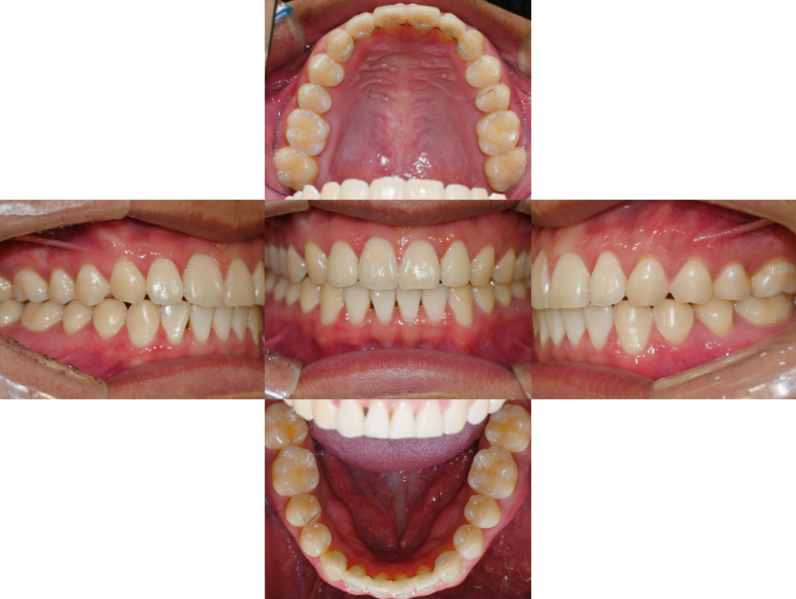

25.02.06

위 악궁이 네모난 양상에서

U shape의 양상을 보여주며

위아래 앞니의 정중선이

잘 맞는 것을 관찰됩니다.

더불어, 우측의 교합 또한

이제는 잘 맞는 것을 확인할 수 있었습니다.